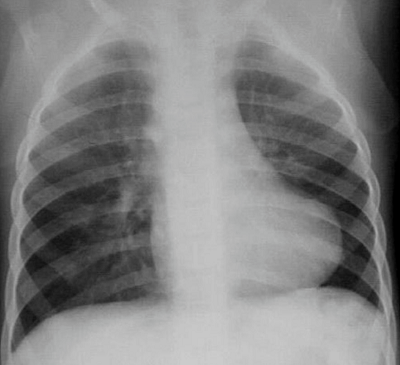

A 48-hour-old newborn child presents with central cyanosis and murmurs detected on precordial exam. He also displays irritability and short rapid breathing for his age.

- Picture: Chest X-ray

- Boot-Shaped Heart Sign

- The boot shape is due to the hypertrophy of right ventricle turning the cardiac apex toward the left lateral side, while misplacement of aorta and missing pulmonary arteries appear as the narrow stem of the boot.

- Tetralogy of Fallot